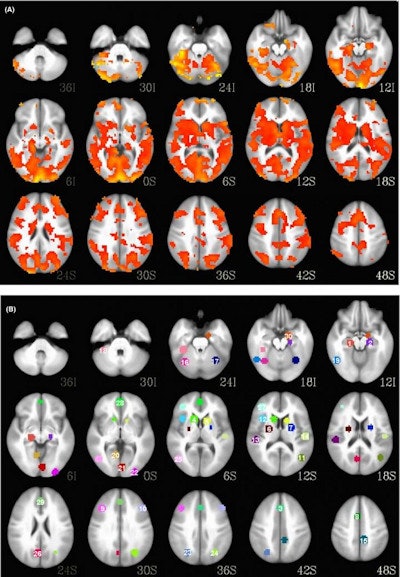

Researchers from the University of Cincinnati (UC) College of Medicine used a machine learning-based system to predict how 20 patients with first-episode bipolar mania would respond to lithium treatment based on an analysis of their baseline functional MRI (fMRI) and proton MR spectroscopy exams.

The team tested LITHIA's performance in 20 patients with first-episode bipolar mania who had been given an adequate trial of lithium over eight weeks and had received both proton MR spectroscopy and functional MRI baseline studies. Of the 20 patients, 15 responded well to the treatment. For the sake of comparison, the researchers also tested eight common classification models currently used in the treatment of bipolar disorder.